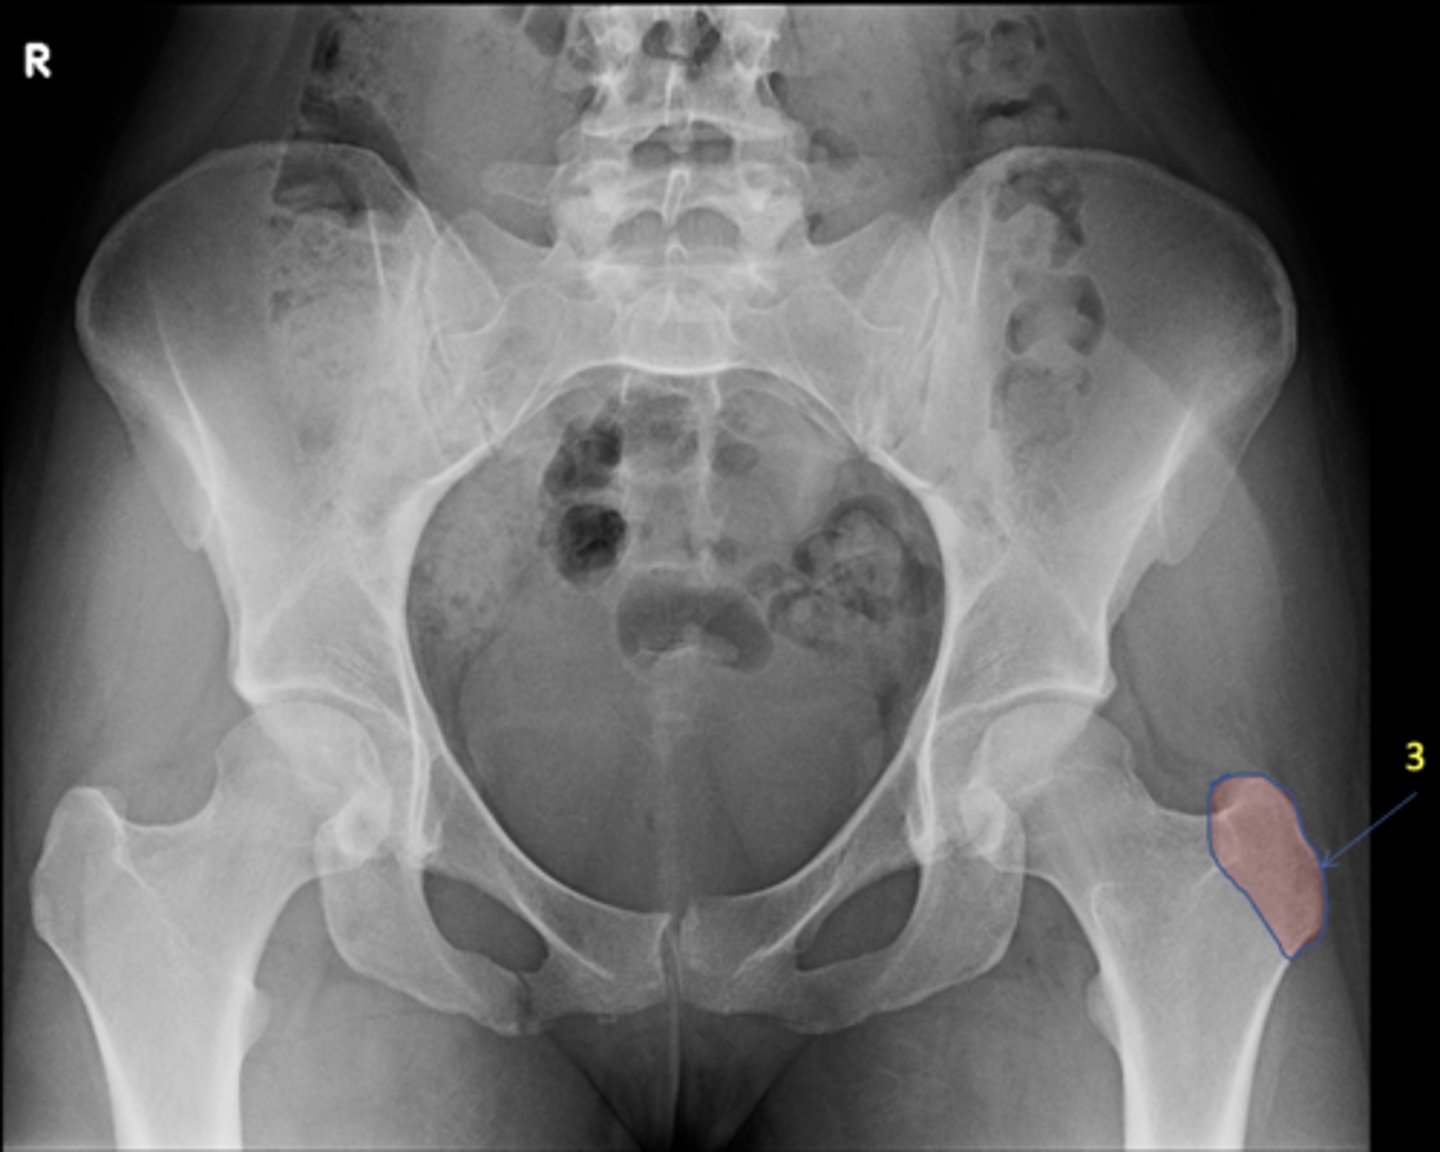

1

AP pelvis

View?

<p>View?</p>